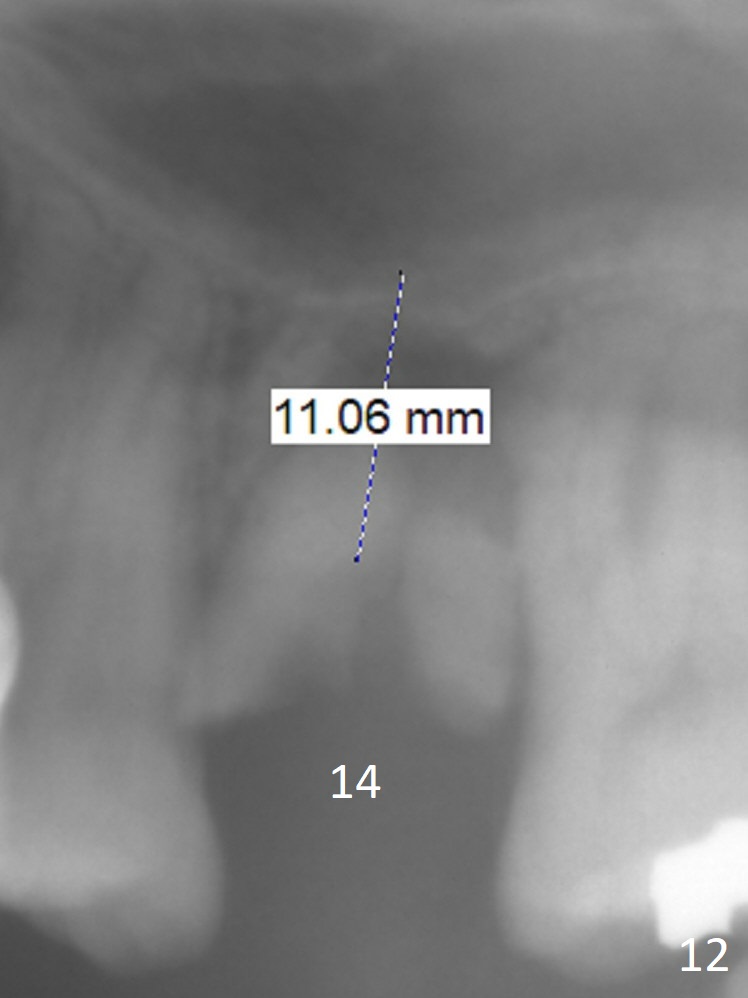

A 54-year-old man is 5 years post liver cancer surgery. After his platelet count returns normal, he wants to take care of his teeth. Most of his molars (#14, 19, 30,31) need extraction and implant placement (Fig.1-4). Although the 2nd premolars on the right are missing (Fig.1,3,4), it seems appropriate to establish 2 molar occlusion on the right (Fig.5,7,8) and 1 on the left (Fig.6,7 (because of #15 supraeruption (Fig.2 arrow))) . Since the residual roots in the lower right quadrant are irritating, implant placement will be done first (Fig.11, Clindamycin), followed by #2,3 (Fig.10) and 14(Fig.12 IBS) and 19 (Fig.12). Use IS drills and 4 and 5 mm stoppers to start osteotomy at #30 and 31, respectively.